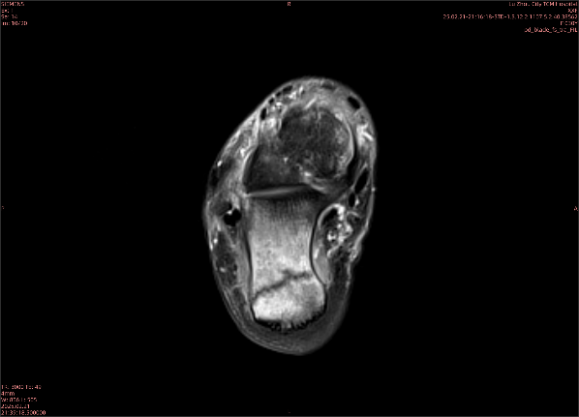

舉例圖像

圖2

專業(yè)解釋看不懂沒關(guān)系,大家看圖1和圖2就可以了,這是同一個(gè)患者跟骨的磁共振和CT圖像,圖1的紅色箭頭指示的黑線就是磁共振圖像顯示的骨折線,一目了然。而對(duì)比圖2的CT圖像上并未顯示異常。